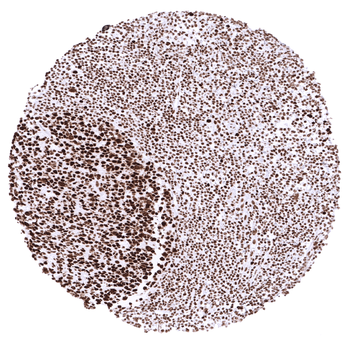

Tonsil.